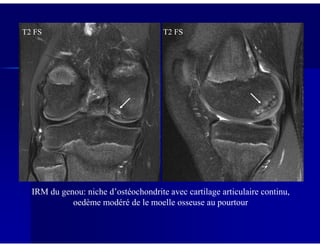

T2 FS T2 FS

IRM du genou: niche d’ostéochondrite avec cartilage articulaire continu,

oedème modéré de le moelle osseuse au pourtour